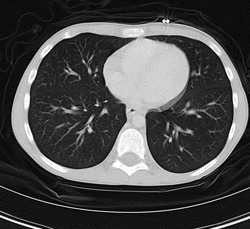

• CT chestPediatric radiologists and technologists specially-trained in pediatric imaging so that your child gets the right test as quickly and accurately as possible.

• Flash CT technology, a pediatric CT scan which uses up to 75% less radiation than a standard adult CT.